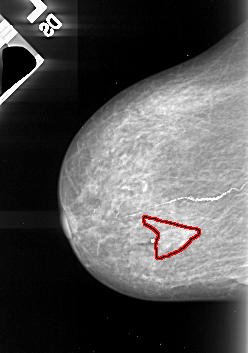

FILE: A_1071_1.LEFT_CC.OVERLAY

TOTAL_ABNORMALITIES 1

ABNORMALITY 1

LESION_TYPE CALCIFICATION TYPE PLEOMORPHIC DISTRIBUTION SEGMENTAL

ASSESSMENT 4

SUBTLETY 2

PATHOLOGY MALIGNANT

TOTAL_OUTLINES 1

BOUNDARY